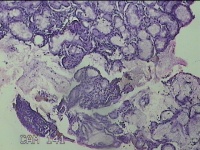

左侧鼻腔病变组织

性别

男

年龄

28岁

临床诊断

1.慢性鼻窦炎 2.鼻中隔偏曲 3.变应性鼻炎

一般病史

反复鼻塞、流涕2月余。

标本名称

大体所见

灰白暗红色组织1.3x0.5x0.3cm一块,表面糜烂,内有少许骨质。

黏膜慢性炎症伴固有腺体反应性增生。